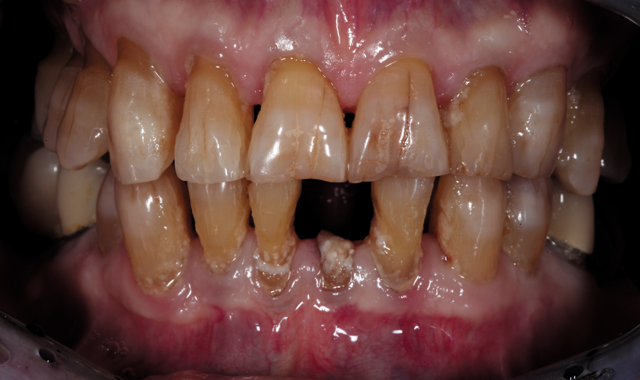

An 88-year-old man presented for restoration of tooth #25, which was fractured and had been endodontically treated (Fig. 1). A thorough intraoral and radiographic examination was performed, which revealed damage to the remaining anterior mandibular teeth incurred over the years as a result of scaling and curettage (Fig. 2). This damage to the

root surface of the lower incisors-which was visible on the radiograph (Fig. 3)-is known as “Riffle-ization.” Described by Dr. Riffle as a technique for removing every last bit of calculus during repeated root scaling, what is now known as “Riffle-izing," ultimately-over the years-changes the shape of the neck of the tooth to resemble an hour glass.

Therefore, based on the clinical and visual evaluation, the preferred treatment would be to restore the fractured #25 with a post and crown and four splinted crowns to restore the anatomy of the four incisors and increase their resistance to both mobility and fracture.

Because the patient was concerned about undergoing lengthy implant treatment and preferred to avoid extraction if possible, the fourth option was selected.

In the past, the splinted crowns required for this case had to be constructed with porcelain-fused-to-metal (PFM).9 Today, the use of zirconia allows for a stronger, more esthetic fixed construction.10 Therefore, after analyzing all of the case information, it was decided with the patient that the final treatment would consist of splinted monolithic zirconia (Zenostar/Wieland, Ivoclar Vivadent) crown restorations.